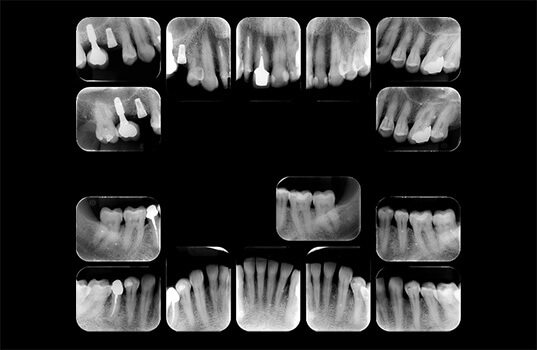

A Radiografia Periapical é um tipo de radiografia odontológica usada para avaliar a saúde do tecido dentário, incluindo a raiz do dente e a área à sua volta, conhecida como a área periapical. É uma ferramenta importante na avaliação de problemas dentários, como cáries, inflamações, infecções, fraturas e outros problemas da raiz do dente.

Na Radiografia Periapical, o paciente coloca a boca na máquina de Raio-X e precisa ficar parado por alguns segundos enquanto a máquina faz a imagem. A imagem resultante mostra a raiz do dente, a área periapical e outras estruturas circundantes, permitindo ao dentista avaliar a saúde do tecido dentário e identificar qualquer problema presente.